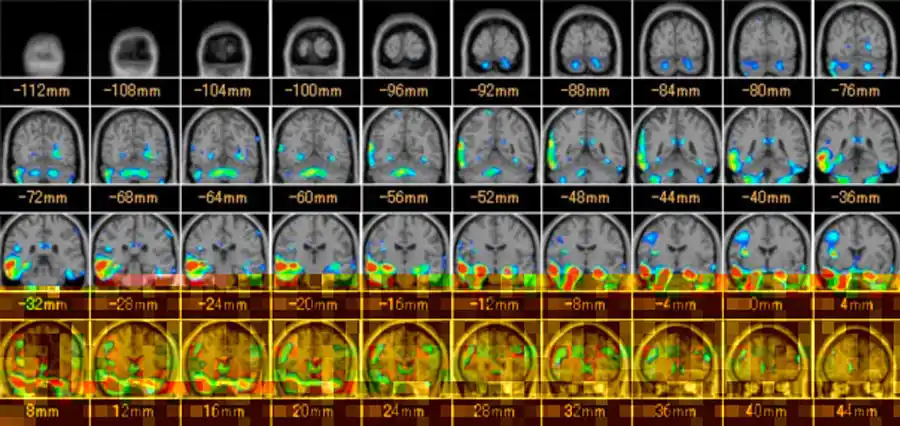

最近では、造影剤を用いて濃度や信号の経時的変化から脳循環を解析する検査法(MRパフュージョン)やMRIでの認知症検査(VSRAD)も増えつつあります。

VSRADとは、早期アルツハイマー型認知症診断支援システムの略語で、人の記憶に関する役目を果たす海馬の萎縮程度を評価するMRI画像処理、解析ソフトのことを言います。

認知症の画像を見ると、左の正常より黒い隙間が目立ち、脳が萎縮していることが分かります。

早期で軽度の萎縮の場合、通常のMRI検査では評価が難しいとされていました。VSRADでは脳の中でも記憶を担当する海馬がどの程度萎縮しているか、%表示し、萎縮程度をカラー表示することによって、軽度の萎縮も評価しやすくし、認知症の早期診断を補助することができます。